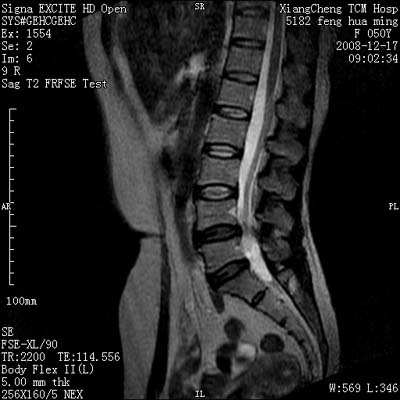

患者,女,50岁,左侧腹股沟及其下方疼痛、酸沉2年。

请各位战友看一下l4-5椎间盘后方椎管内是病灶吗?马尾神经到此处是不是终止了?

腰45椎间盘突出,后部影像可能是硬膜囊粘连引起的

l4/5椎间盘突出。后方硬膜囊受压改变。另外,该病人是否并发子宫肌瘤啊

腰45椎间盘突出,马尾终丝聚集:考虑蛛网膜炎症粘连

l4-5轻突,黄韧带增厚,蛛网膜炎症粘连可能

l4/5椎间盘突出;马尾终丝聚集,考虑蛛网膜炎所致。